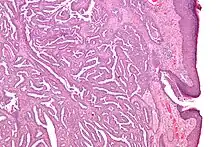

| Micrograph of a nipple adenoma. H&E stain. | |

Once excised, the macroscopic appearance of nipple adenomas is of a poorly defined nodular mass. The microscopic appearance can be quite bizarre, and may be misinterpreted as a carcinoma. Nipple adenomas usually have a rounded outline at low magnification, and at higher magnification can be seen to consist of a haphazardly arranged mass of proliferating tubular structures composed of epithelial and myoepithelial cells within varying amounts of fibrous stroma. The epithelial cells are usually columnar, but the columnar epithelial cells can undergo apocrine or squamous metaplasia. Mitotic figures and necrosis are not commonly seen.[1]